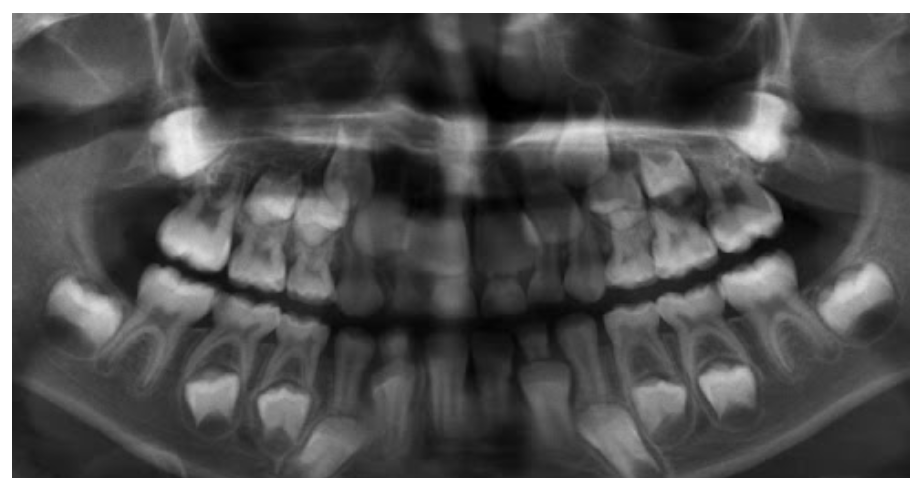

1.lower adult CI there? YES, so def 6-7

1. Upper Ad. Ci there? NO, so either 6-7 or under

Last molar crown not really formed so 6?

NOTE- THE 8’s - crown starts developing at 9 yo.